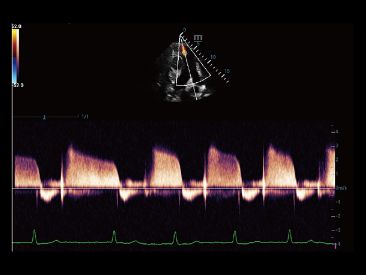

Desde que se fundó la compa?ía, Mindray ha explorado incansablemente nuevas formas de mejorar la confiabilidad del diagnóstico. Con la revolucionaria tecnología de ZONE Sonography?, la nueva plataforma ZST+ de Resona?7 lleva la calidad de la imagen por ecografía a un nivel superior mediante el procesamiento de datos de canal y la adquisición de zona.

Además de la calidad de imagen de primer nivel, Resona?7 también mejora las capacidades de investigación clínica con el revolucionario V?Flow para la evaluación hemodinámica vascular y con la adquisición de planos más inteligente a partir de conjuntos de datos 3D para el diagnóstico del SNC fetal. Al combinar el funcionamiento multitáctil basado en gestos más intuitivo y todas las características clínicas esenciales, Resona?7 realmente lidera las novedades en innovación de ecografías.